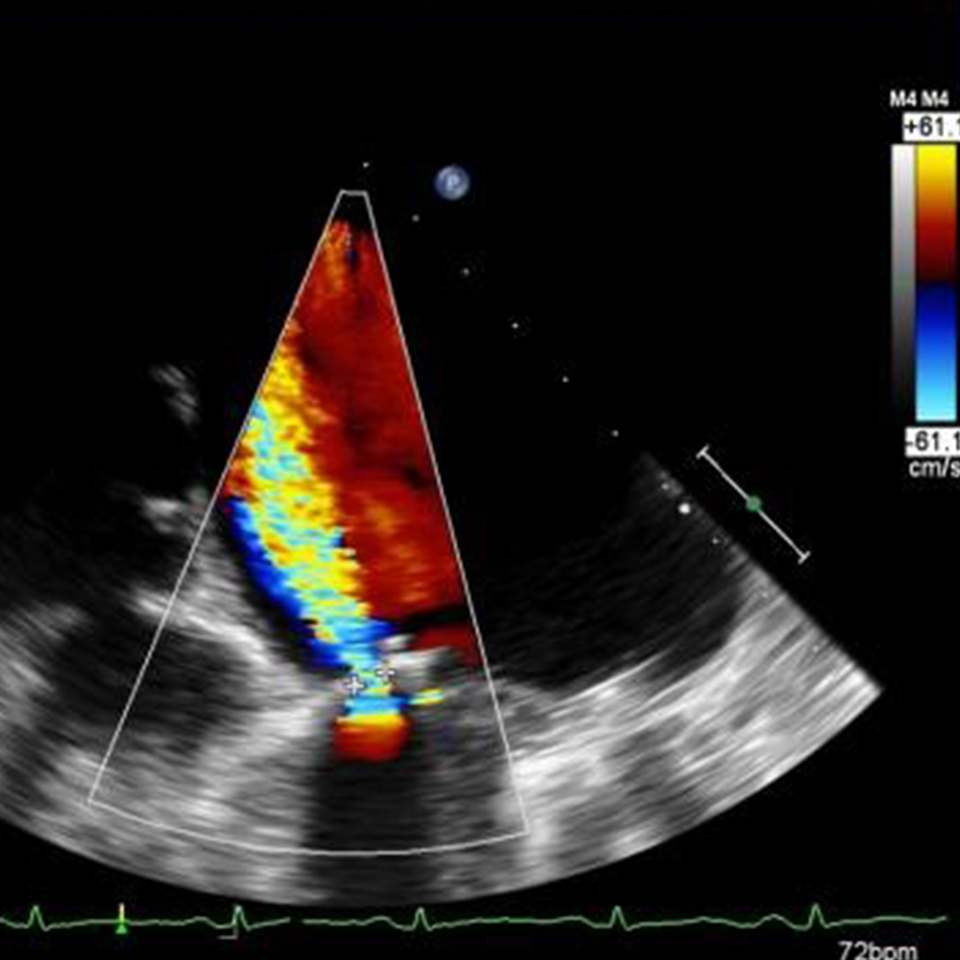

ECHOCARDIOGRAM An echocardiogram, or echo, is an ultrasound scan with the purpose of looking at the heart and nearby blood vessels. Reach out for more information! Home » Services » Echocardiogram